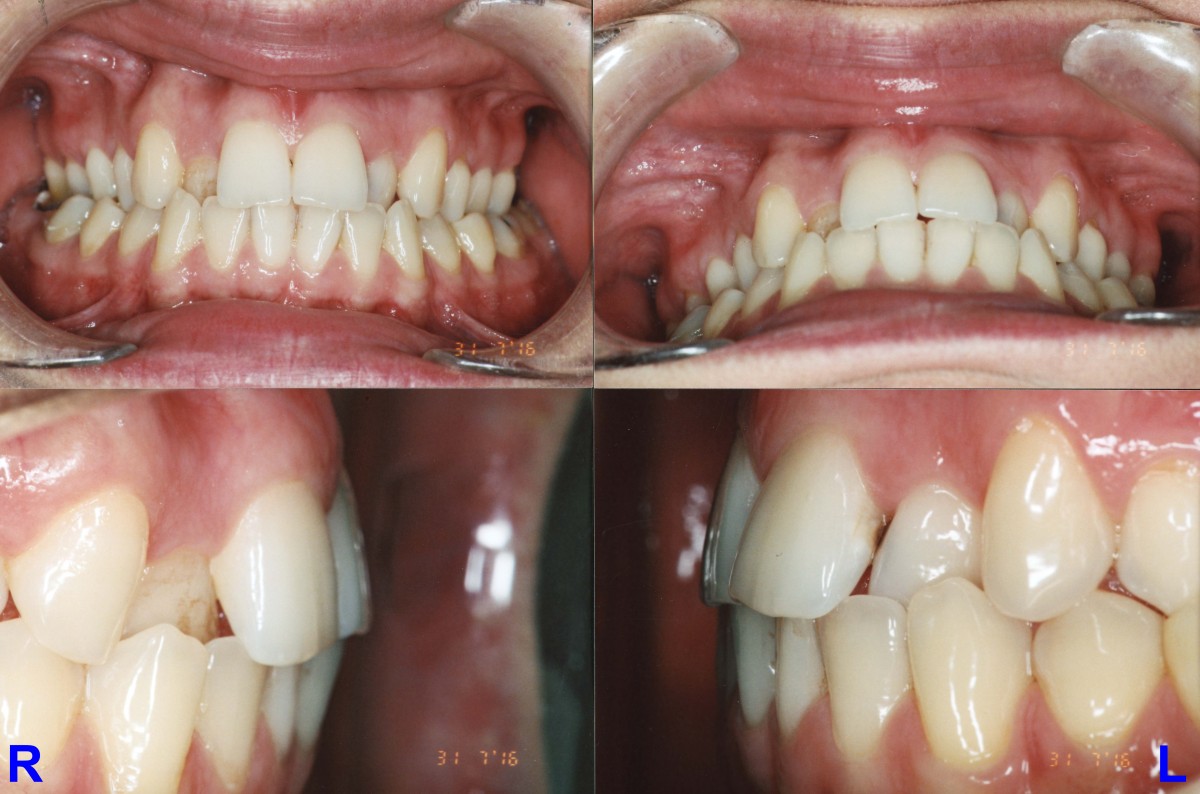

Pacient, 26 ani. Caz nonextracționist, Expander Maxilar + aparate ortodontice fixe bimaxilare.